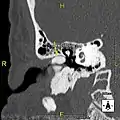

Normal ear canal